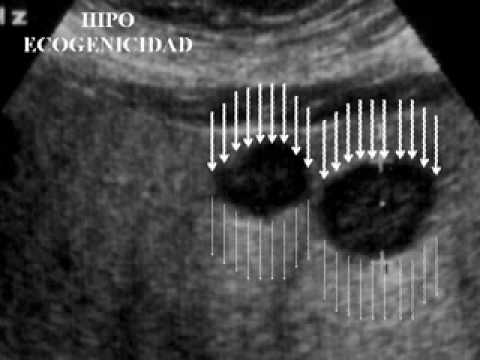

Temas de Ginecología y Obstetricia, Ultrasonido, Colposcopía, Cirugía Ginecológica, Historia de la Medicina, Enseñanza de la medicina